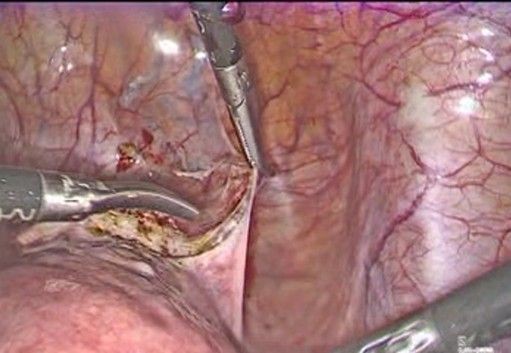

- Exposure of the lower uterine segment (Figure 3-5): the uterus is moved anteriorly or laterally to expose the utero-cervical junction (key anatomy: Anterior aspect of the lower uterine segment and cervix, vesicouterine fold, and peritoneal reflection of the bladder). The vesicouterine peritoneum is carefully incised and dissected, moving the bladder caudally to expose the anterior aspect of the cervix.

Figure 4: Careful incision of the bladder peritoneum

Figure 5: the bladder I moved caudally